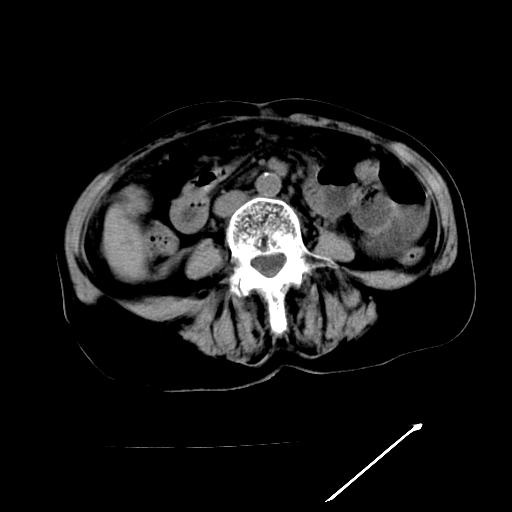

以下是引用卜一在2009-4-7 5:06:00的发言:[br]左右肝内胆管结石伴扩张合并胆系感染;不除外胆管细胞癌可能。支持! [br] [br]

以下是引用随光逐影在2009-4-7 8:21:00的发言:[br]肝内外胆管多发性结石并肝内外胆管扩张;胆系感染。